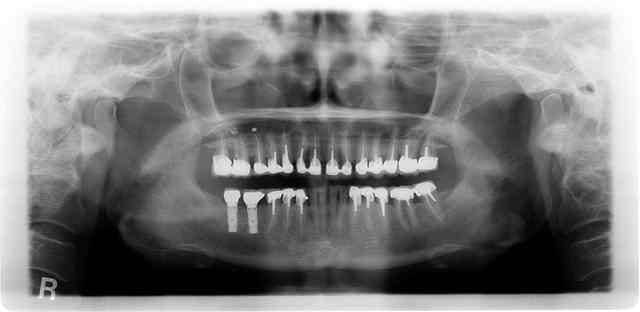

radio en 2011

ça va non ?

012011 wsypdn - Eugenol